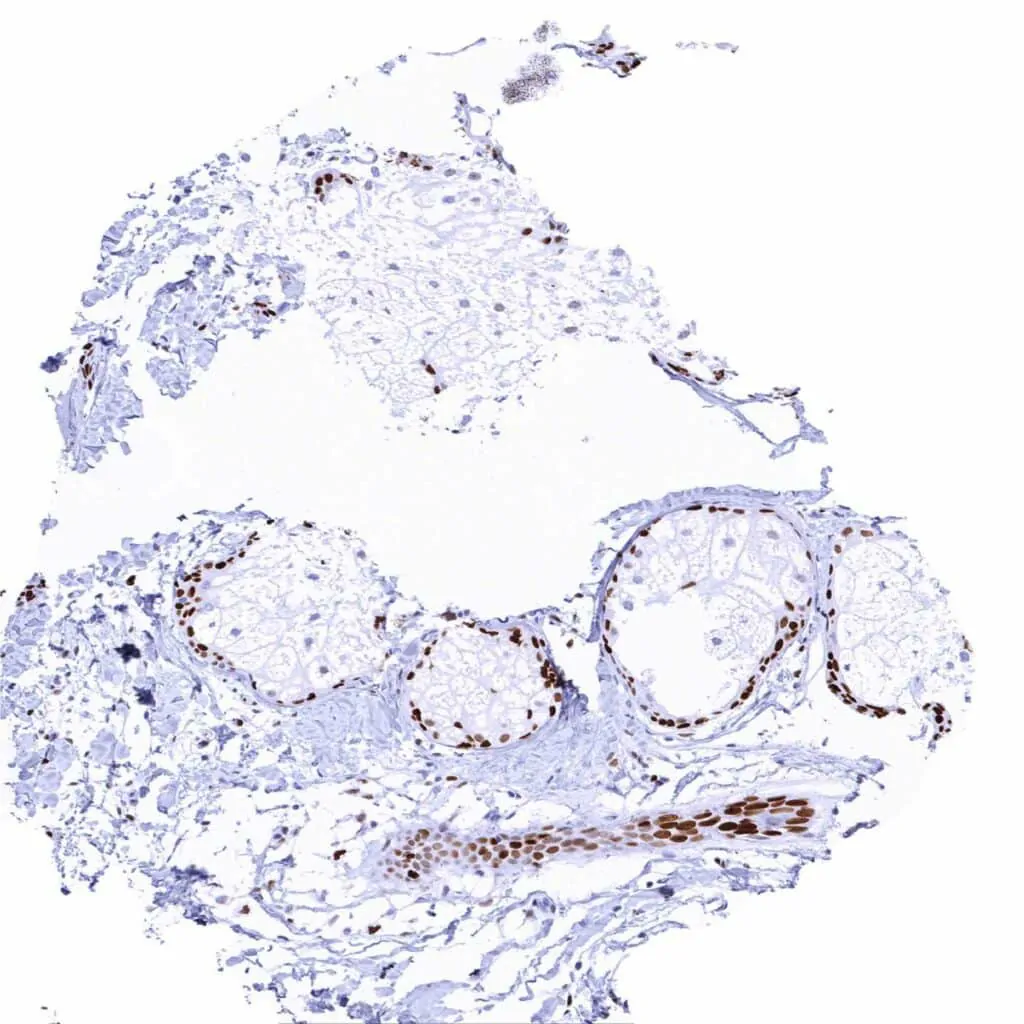

Testis – Most spermatogonia and spermatocytes show strong MCM2 positivity